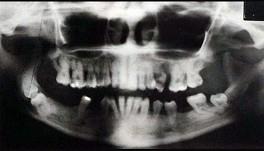

问题 关于快速进展性牙周炎,哪项正确()

选项 A.发病年龄青春期至25岁之间 B.病损好发于第一恒磨牙和上下前牙 C.有严重及快速的骨破坏,然后破坏过程自然停止或显著减慢 D.所有患者都有中性粒细胞及单核细胞的功能缺陷 E.本病极少伴有全身症状

答案 C